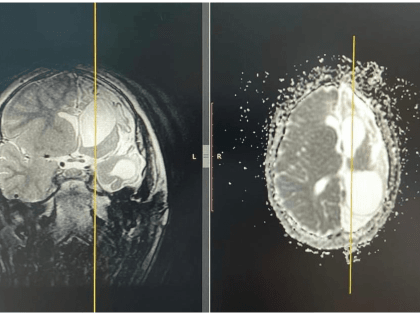

В Башкирии сделали уникальную операцию пятилетнему ребенку

Медики республиканской детской клинической больницы в Уфе провели уникальную операцию пятилетнему мальчику.